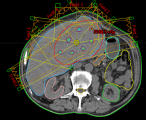

病例展示三:胰腺癌

腺癌病灶压迫并侵润十二指肠,十二指肠梗阻不能正常进食,患者留置营养管及胃肠减压管;伴胆道梗阻诱发黄疸,留置PTCD引流管。诊断:1.胰头恶性肿瘤 cT4N0M0 III期 KPS评分:80分;2.十二指肠不全梗阻;3.梗阻性黄疸,4.心律失常 室性期前收缩5. 慢性心力衰竭6.陈旧性心肌梗死7.冠状动脉粥样硬化性心脏病8. 缺血性心肌病。治疗:2024-05月开始吉西他滨+白蛋白紫杉醇化疗4周期,碳离子放疗剂量:PTV 36Gy(RBE)/9fx,后缩野补量,剂量:PTV boost 18Gy(RBE)/4fx,4.5Gy(RBE)/fx。

疗效评价